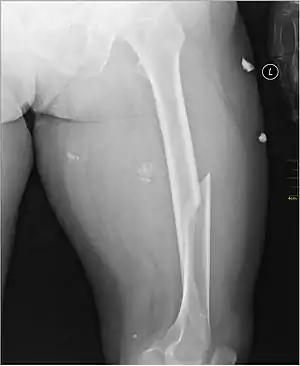

كسر الفخذ (بالإنجليزية: Femoral fracture) عبارة عن كسر عظم الفخذ، وعادةً ما يتم تحمل الكسر في حالات الصدمات شديدة التأثير مثل حوادث السيارات نظرًا للكمية الكبيرة من القوة اللازمة لكسر هذه العظمة، وتتم إدارة كسور الجدل (عظم وسط الفخذ) بشكل مختلف عن تلك الموجودة في الرأس والرقبة والمدور (انظر كسور الورك).

يمكن تصنيف الكسر على أنه مفتوح الذي يحدث عندما تبرز شظيات العظم عبر الجلد أو يكون هناك جرح مفرط يتغلغل في العظم، وتسبب هذه الأنواع من الكسور المزيد من الضرر للنسيج المحيط ونكون أقل عرضة للشفاء بشكل صحيح وأكثر عرضة للإصابة بالعدوى.

تكون الكسور واضحة بشكل شائع لأن كسور الفخذ غالباً ما تسببها صدمة عالية الطاقة،[3] علامات الكسر تشمل تورم وتشوه وفصر في الساق،[4] وتعد إصابة الأنسجة الرخوة واسعة النطاق والنزيف والصدمة من الأمور الشائعة،[5] وأكثر الأعراض شيوعًا هو الألم الشديد الذي يمنع حركة الساق.[6]